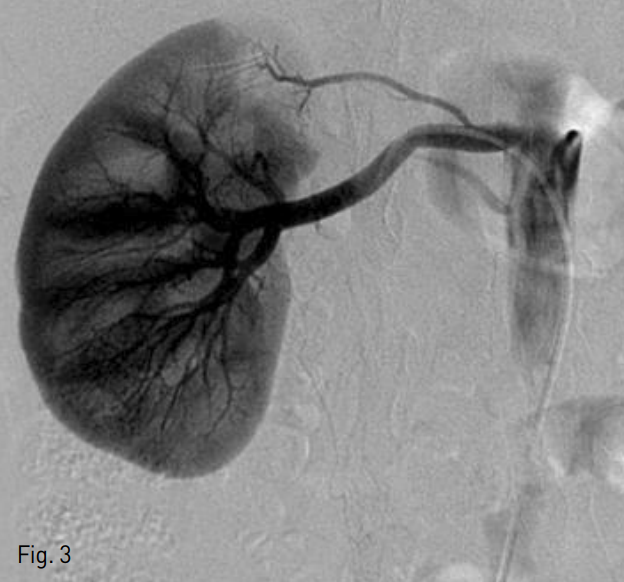

본원에서 시행한 신장 CT의 배출기 영상에서 오른쪽 중간 뒤쪽 신배에서 작은 저감쇠의 병변을 관찰할 수 있었고 (Fig. 2), 타 병원에서 이전에 시행한 신장 CT 를 후향적으로 검토했을 때 역시 같은 위치에 의심 병변을 찾을 수 있었다.

Fig. 2

Coronal recons tructed image of kidney CT excretory phase shows small low attenuating lesion within the right mid-posterior calyx (arrow).